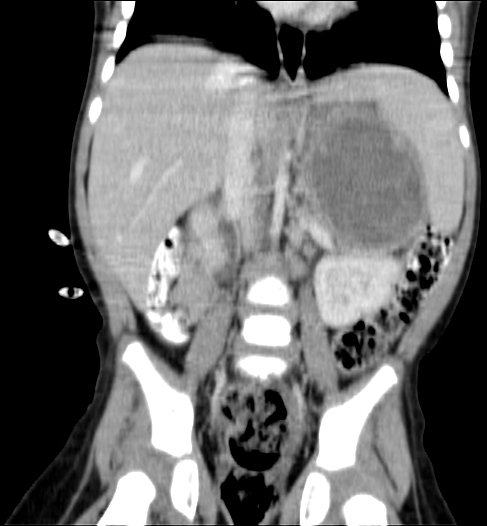

CT (CAT) scan 25 August 2011